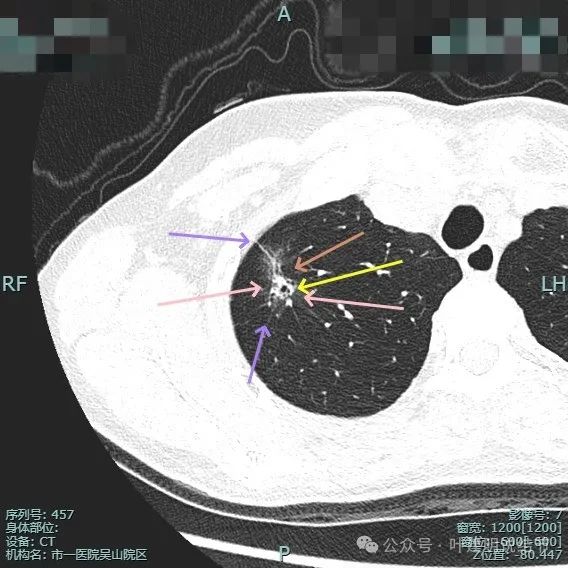

实性成分较明显,扩张的支气管壁显得僵硬,表面分叶明显,边缘细毛刺明显。

毛刺征、混合密度且实性成分杂乱、支气管扩张僵硬、分叶征明显。

血管进入、表面分叶、胸膜牵拉、磨玻璃成分明显、实性部分缺乏收缩力但显杂乱,整体轮廓与边界清。